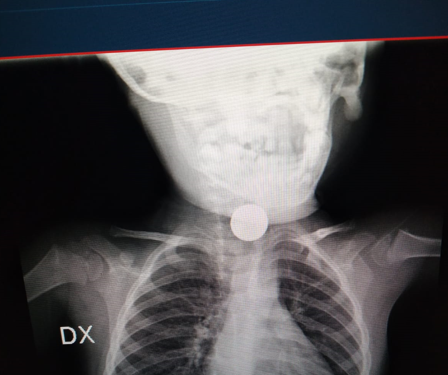

Arrivato al presidio del Vomero vengono effettuati nuovi controlli e, da un attento esame radiografico, si capisce che il corpo estraneo fermatosi in esofago è una disk battery che, ormai, è tenacemente aderente all’esofago con una progressiva necrosi dei tessuti.